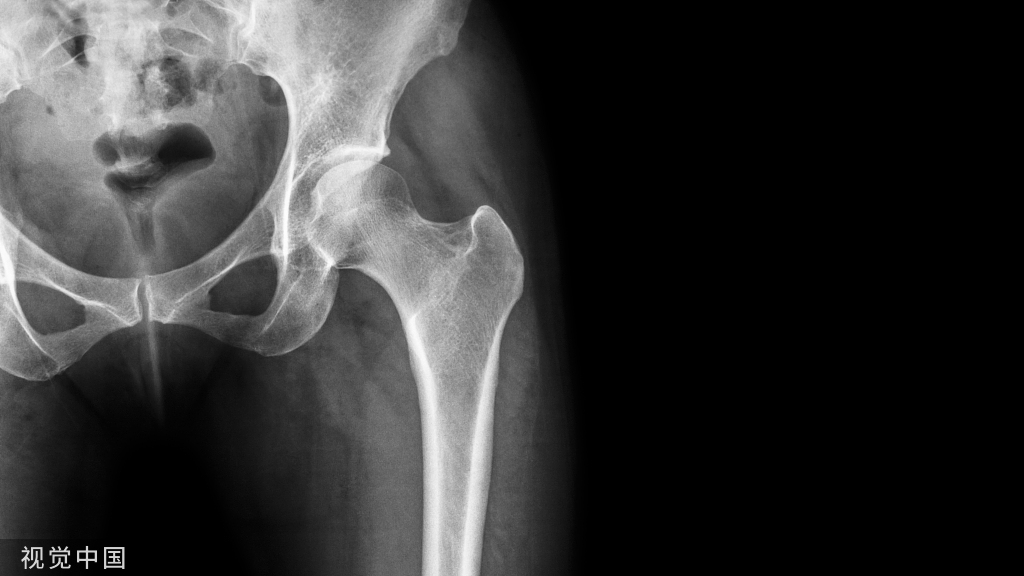

(1)社会老龄化的到来,人体随着年龄的增加,身体的各个器官和系统功能逐渐下降,而这其中以骨质疏松和骨关节病最为突出。前者表现为骨质脆性增加,在受到外力作用下极易发生骨折 ;后者则主要表现为慢性关节疼痛,关节功能障碍和丧失。这些病变均严重影响老年人晚年身体健康和生活质量。随着经济水平的提高,接受人工关节置换的高龄患者越来越多,对绝大多数老年患者都能取得良好效果,故这种手术治疗方式已在临床广泛推广。因此,人工关节置换术在老龄化社会中的客观需求性将会显得愈来愈突出。

(2)老年患者人工关节置换术时骨水泥反应综合征的发生情况 :由于高龄患者多数存在骨质疏松,在人工关节置换手术中经常需要用到骨水泥( bone cement)。目前常用的生物骨水泥分为生物相容性较差的PMMA 骨水泥和生物相容性较好的磷酸钙骨水泥。随着骨水泥的广泛应用,骨水泥对心血管的影响,以及由此产生的“骨水泥反应综合征”在手术期间时有发生。Woo等综合文献报道后发现,骨水泥综合征导致心搏骤停的发生率为0.6% ~10%,病死率为0.02% ~0.5%。目前,无论手术医师,还是麻醉医师,均对老年患者人工关节置换术时骨水泥反应综合征的发生高度警惕。